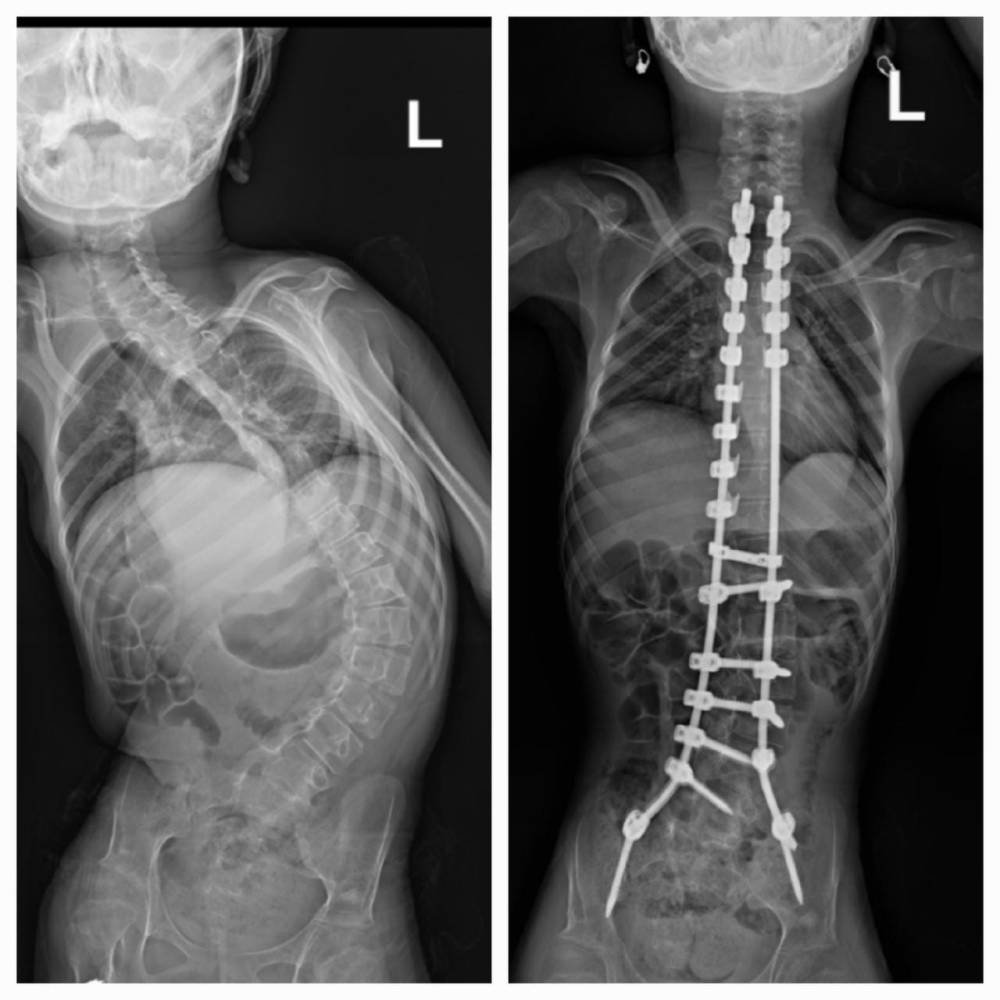

ومن الحالات التي أجراها المركز، مؤخراً، حالة لمريضة في عمر الـ14 سنة، كانت تعاني من الشلل الدماغي وانحراف شديد وميلان في العمود الفقري، ليتم بعد الإجراء تقويم العمود وتعديله وبشكل كامل، وبسرعة وكفاءة عالية، حيث لم تستغرق العملية سوى 4 ساعات فقط، تماثلت بعدها المريضة للشفاء وأصبحت قادرة على الاعتماد على نفسها، وغادرت المستشفى بعد 4 أيام من إجراء العملية.

وأوضح البروفيسور عبدالمنعم الصديقي أن هذا المرض، يؤدي أحياناً إلى صعوبة في حركة المريض، وكذلك صعوبة في التفاهم والتواصل مع الآخرين، وغالبا ما تصاحبه انحرافات في العمود الفقري، نتيجة الضعف في العظام وفي العضلات، وهذا بدوره يمثل تحدياً في إجراء المثبتات واستخدام الأدوات الجراحية وتثبيت البراغي، بجانب تحدي تقويم العمود الفقري، مشيراً إلى أن الانحرافات غالباً ما تأخذ شكلاً صلباً بسبب تصلب العمود الفقري وعدم مرونته، ويؤدي ذلك إلى ميلان في الظهر وعدم توازن في الكتفين، كذلك عدم التوازن في الحوض لدى المريض.

وحول مراحل تشخيص مرض الجنف، أوضح البروفيسور عبدالمنعم الصديقي أن طريقة التشخيص في الحالات المختلفة تتطلب الكشف السريري المبدئي على الظهر وارتفاع الكتفين، وقد يطلب الطبيب المختص إجراء الأشعة السينية لتشخيص المرض وقياس زاوية الانحراف، وكذلك أشعة مقطعية وأشعة الرنين، للتأكد من سلامة الحبل والعمود الفقري في بعض الحالات، وذلك قبل مباشرة العلاج اللازم.